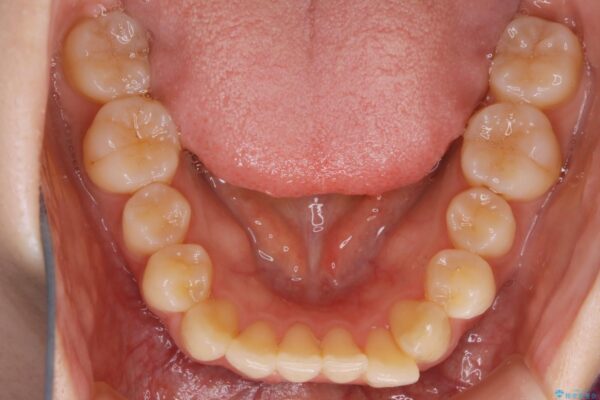

下の前歯のガタつきが気になるとご来院された患者様です。

インビザラインのライトパッケージにて、歯列拡大とディスキング(IPR)をを行いスペースをつくり非抜歯で治療を行いました。

歯並びが悪くなる原因の一つに「歯列弓の狭窄」というものがあります。

奥歯や前歯が内側(舌側)に倒れ込んでしまったり、歯が生えてくる位置が内側になってしまうことにより歯並びのアーチが狭くなってしまうことを言います。

このような場合、歯並びのアーチを拡大してあげるだけでもガタつきを無くすためのスペースがかなり作れることがあります。